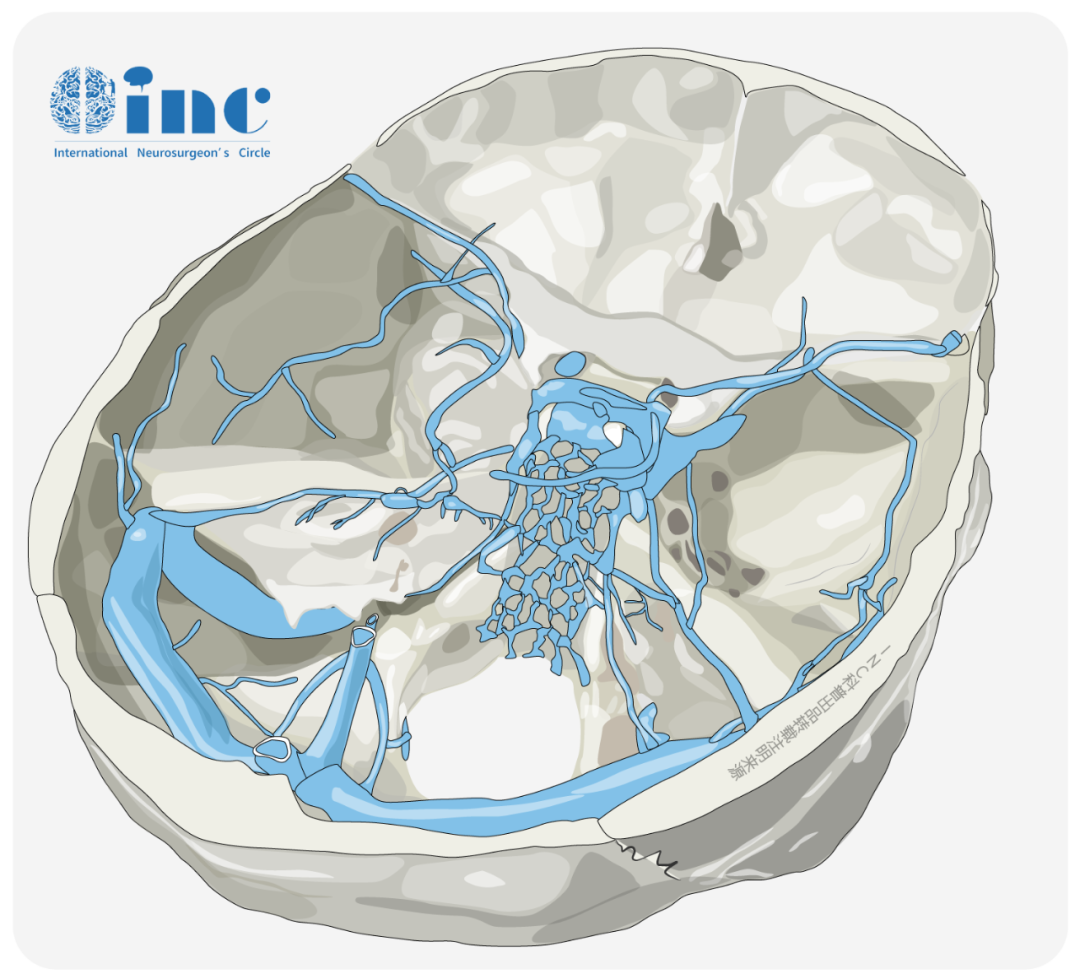

国际知名神经外科期刊《Journal of Neurosurgery》发表INC脑血管专家巴特朗菲教授的脑干脑桥海绵状血管瘤135例手术经验,总结系列手术案例的病变分型、手术入路、切除情况及术后并发症、恢复情况等...